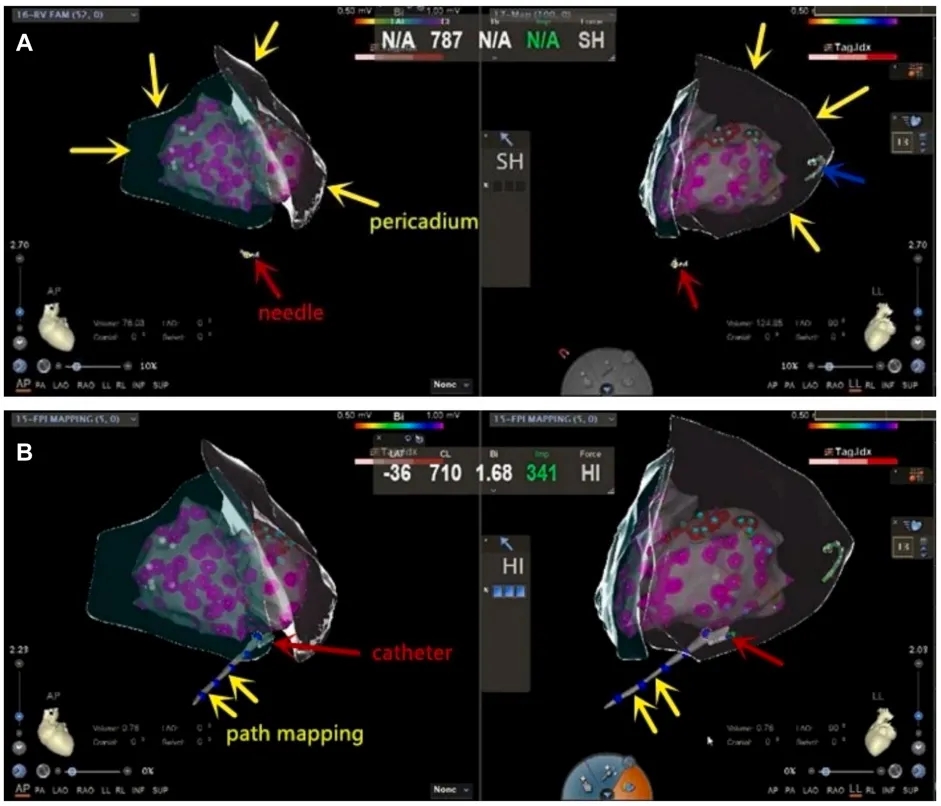

随后对VT进行了射频消融,包含30分钟的心内膜消融和40分钟的心外膜消融。患者术前存在反复且频繁的室性早搏,以及短暂的VT发作。VT发作期间的体表心电图提示心律失常起源于左心室顶部。在心内膜标测前进行了心外膜标测,使用CARTO在3D-EAM系统中构建三维解剖模型,并通过射频导管收集相关数据。整个手术消融过程中无并发症发生,随后行异丙肾上腺素负荷试验未诱发VT,证实了手术的成功(图 4)。

图4:经心包途径消融心外膜室速

➤ ICE/3D引导下心包穿刺术和经心包途径消融流程。

(A)在前后位和左侧位投影视图的动态监测下,针尖逐渐向心外膜推进,直至达到精确重叠,红色箭头表示CARTO系统定位的双极导管,代表穿刺针尖;黄色箭头表示通过CARTO系统使用ICE结合EAM构建的心外膜解剖模型;蓝色箭头表示位于冠状窦中的标测电极。(B)黄色箭头描绘了消融导管进入心包间隙时的轨迹,而红色箭头表示消融导管在该腔内的位置。